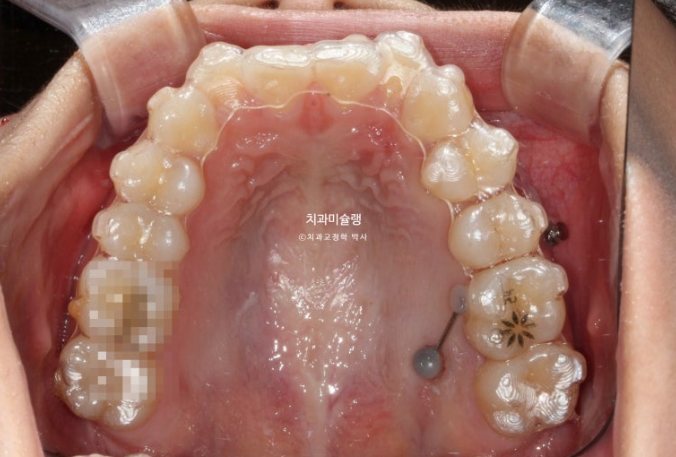

24.12

겨울방학때 입국하여 내원했을 당시 모습입니다.

어금니 후방이동을 위해 교정용 나사 미니스크류가 안팎으로 심겨져있습니다.